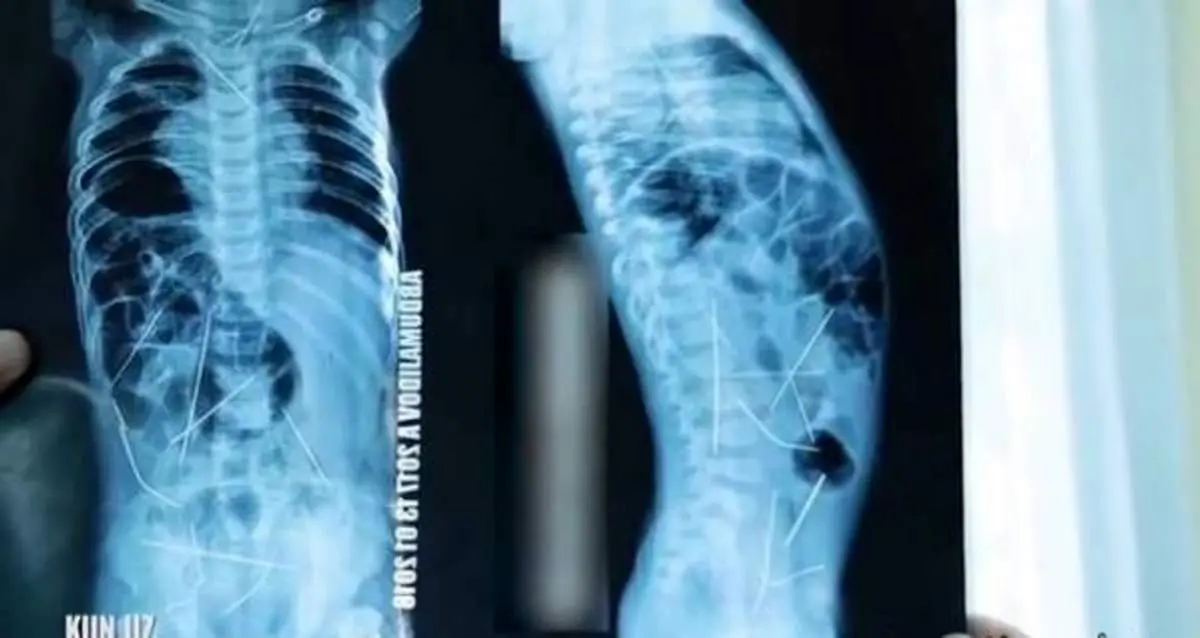

کشف تعداد زیادی سوزن خیاطی داخل بدن یک نوزاد! + عکس

مشتی سوزن داخل بدن کودک 11 ماهه فرو شدن بود اما مادر کودک از این مسئله اطلاعی نداشت ، عکسبرداری ها وضعیت وحشتناک کودک را فاش کردند.

پزشک بعد از معاینات اولیه کودک خردسالی که به دلیل تب شدید به بیمارستان آورده بودند عکسبرداری کامل تجویز کرد تا علت مشکوک را شناسایی کند ، نتایج عکسبرداری ها یک فاجعه بود چرا که اعضای داخلی و حساس کودک با سوزن های تیز احاطه شده بودند.؛ نزدیک بودن سوزن ها به قلب ، مثانه ، روده بزرگ و گردن کودک وضعیت او را به این وخامت رسانده بود . کودک به سرعت برای جراحی آماده شد تا ار مرگ او جلوگیری شود.

تیمی از متخصصان و جراحان بعد از 9 ساعت تلاش موفق شدند تمامی سوزن ها را از بدن کودک خارج کنند ، یکی از جراحان متخصص قلب بود که 3 سوزن را از داخل سینه کودک بیرون کشید همچنین 9 سوزن هم از شکم و 1 سوزن هم از گردن بیمار خارج شد تا شمار سوزن های خارج شد به 13 برسد و باقی در مراحل بعد خارج شود.